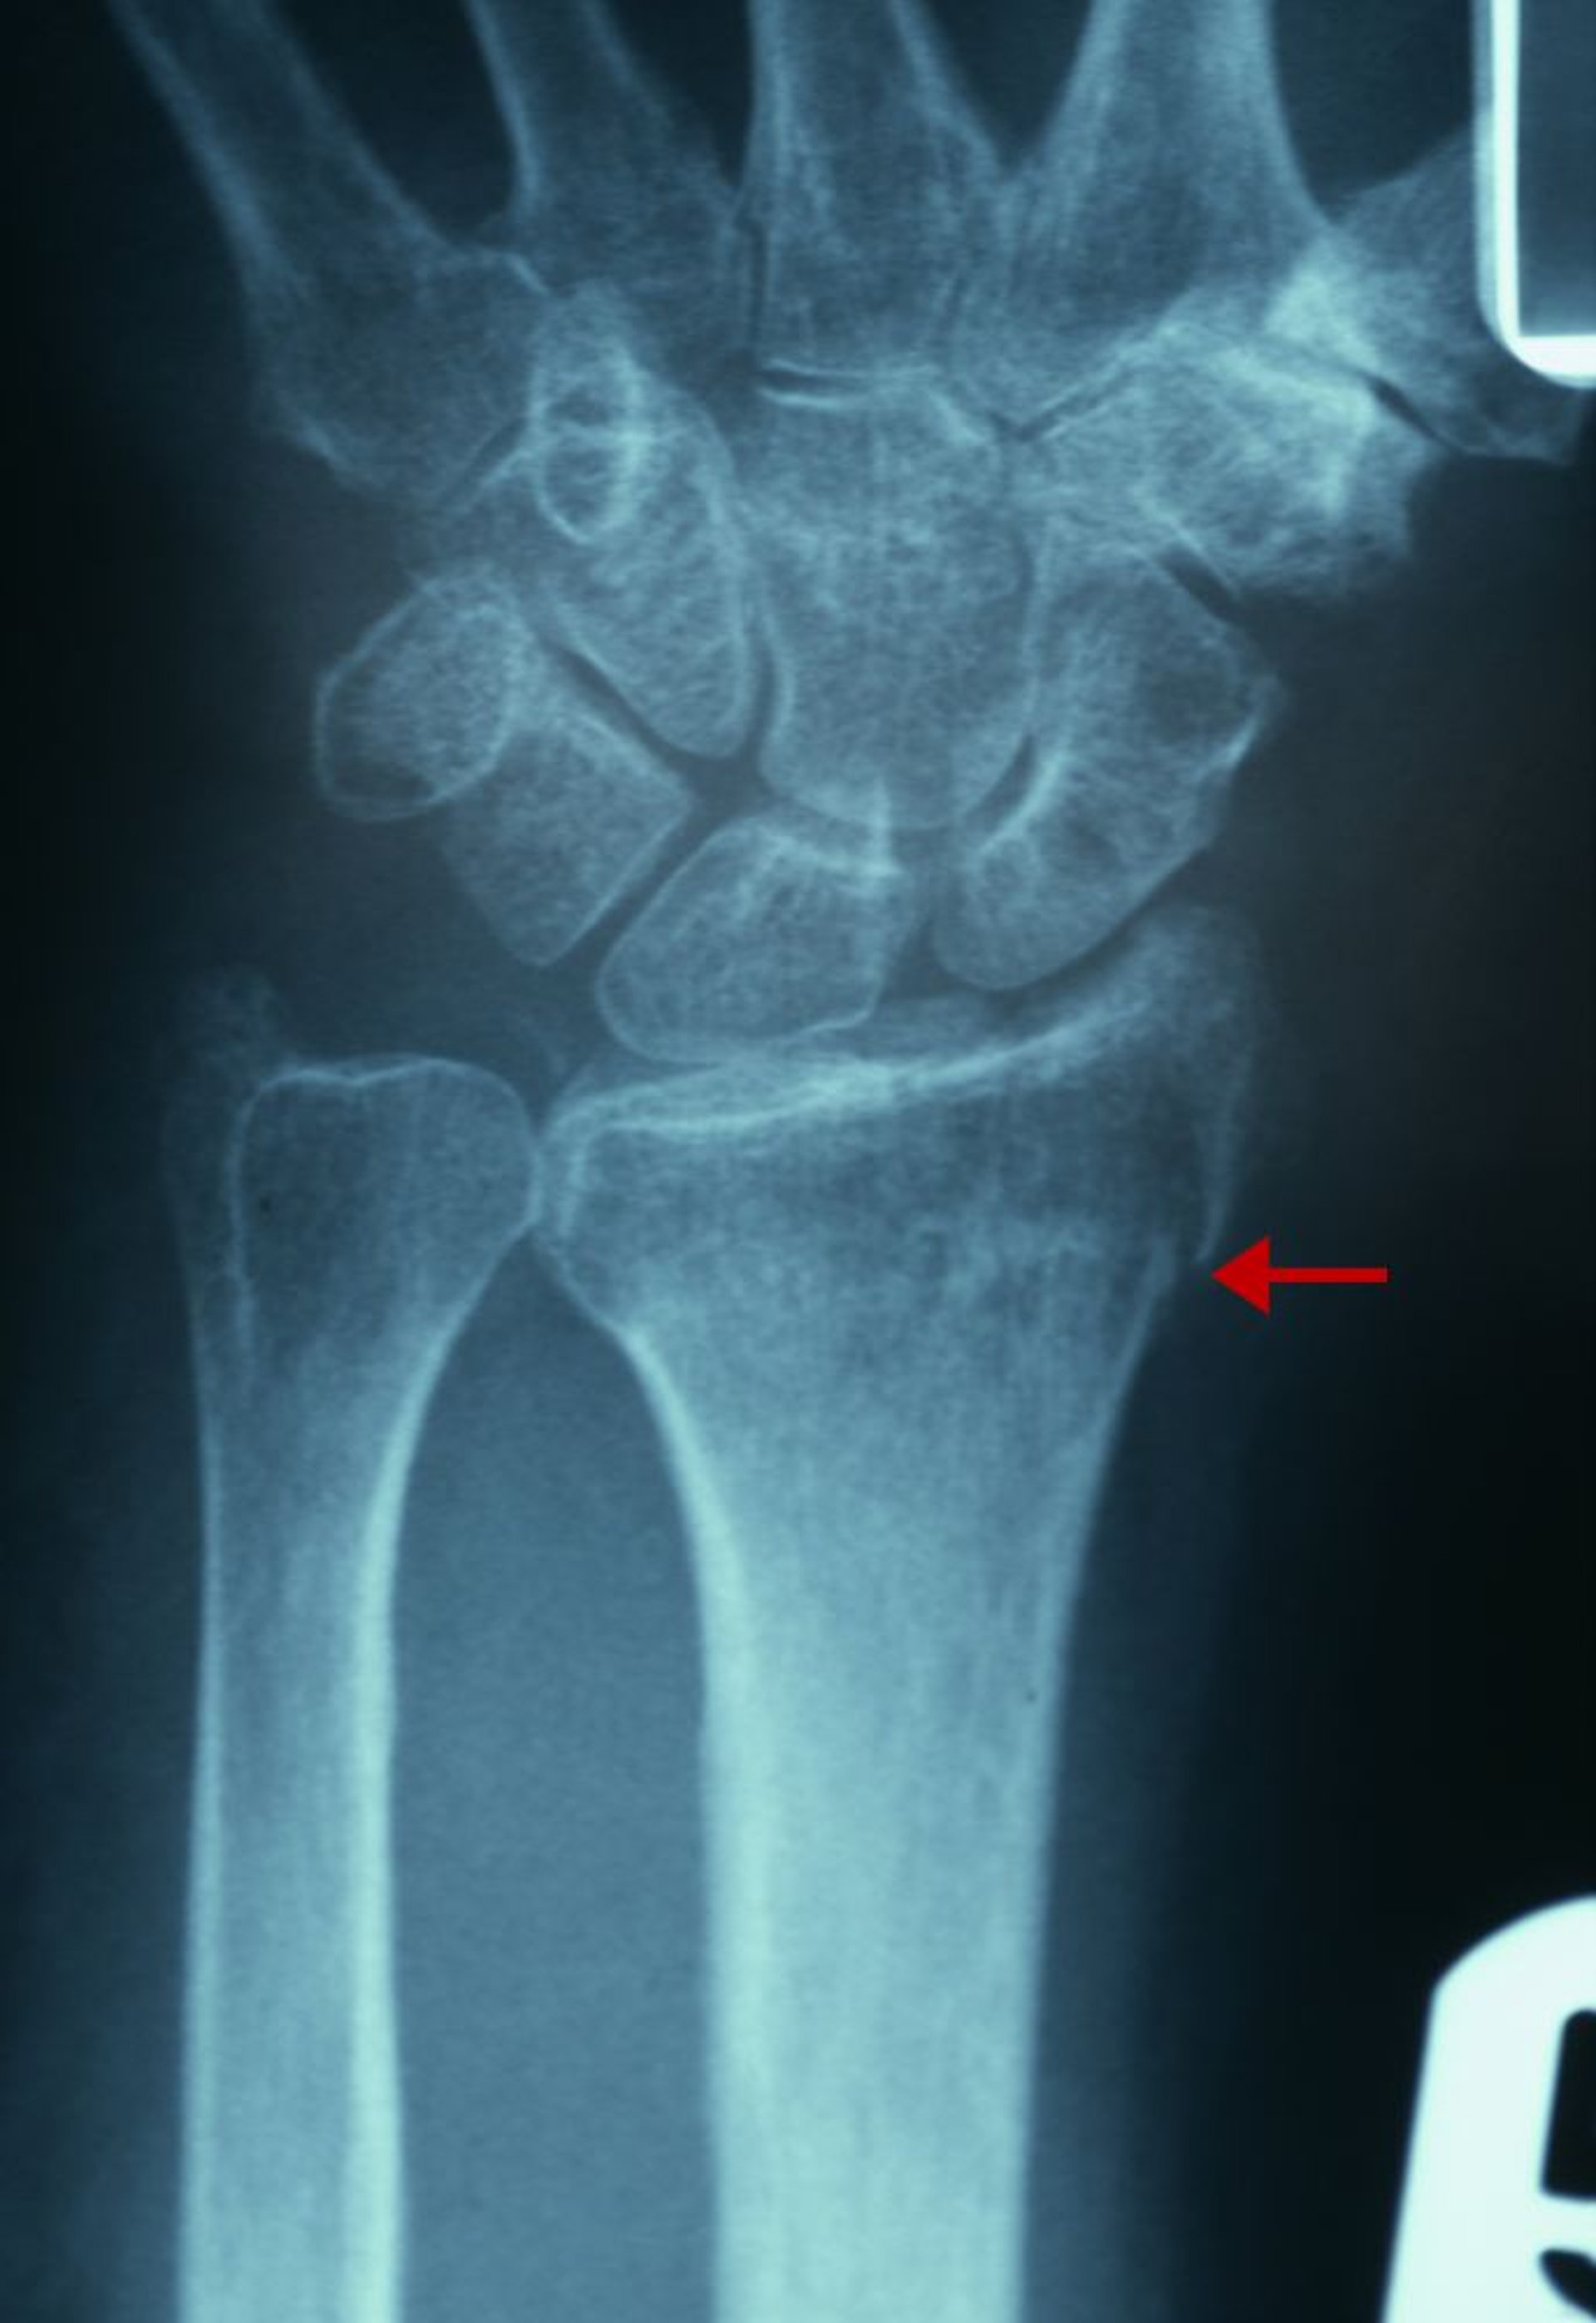

Fratura distal do rádio discreta

Evidências radiográficas dessa fratura são uma solução de continuidade da cortical na face radial da extremidade distal (seta) e o aumento da densidade trabecular do segmento distal do rádio.